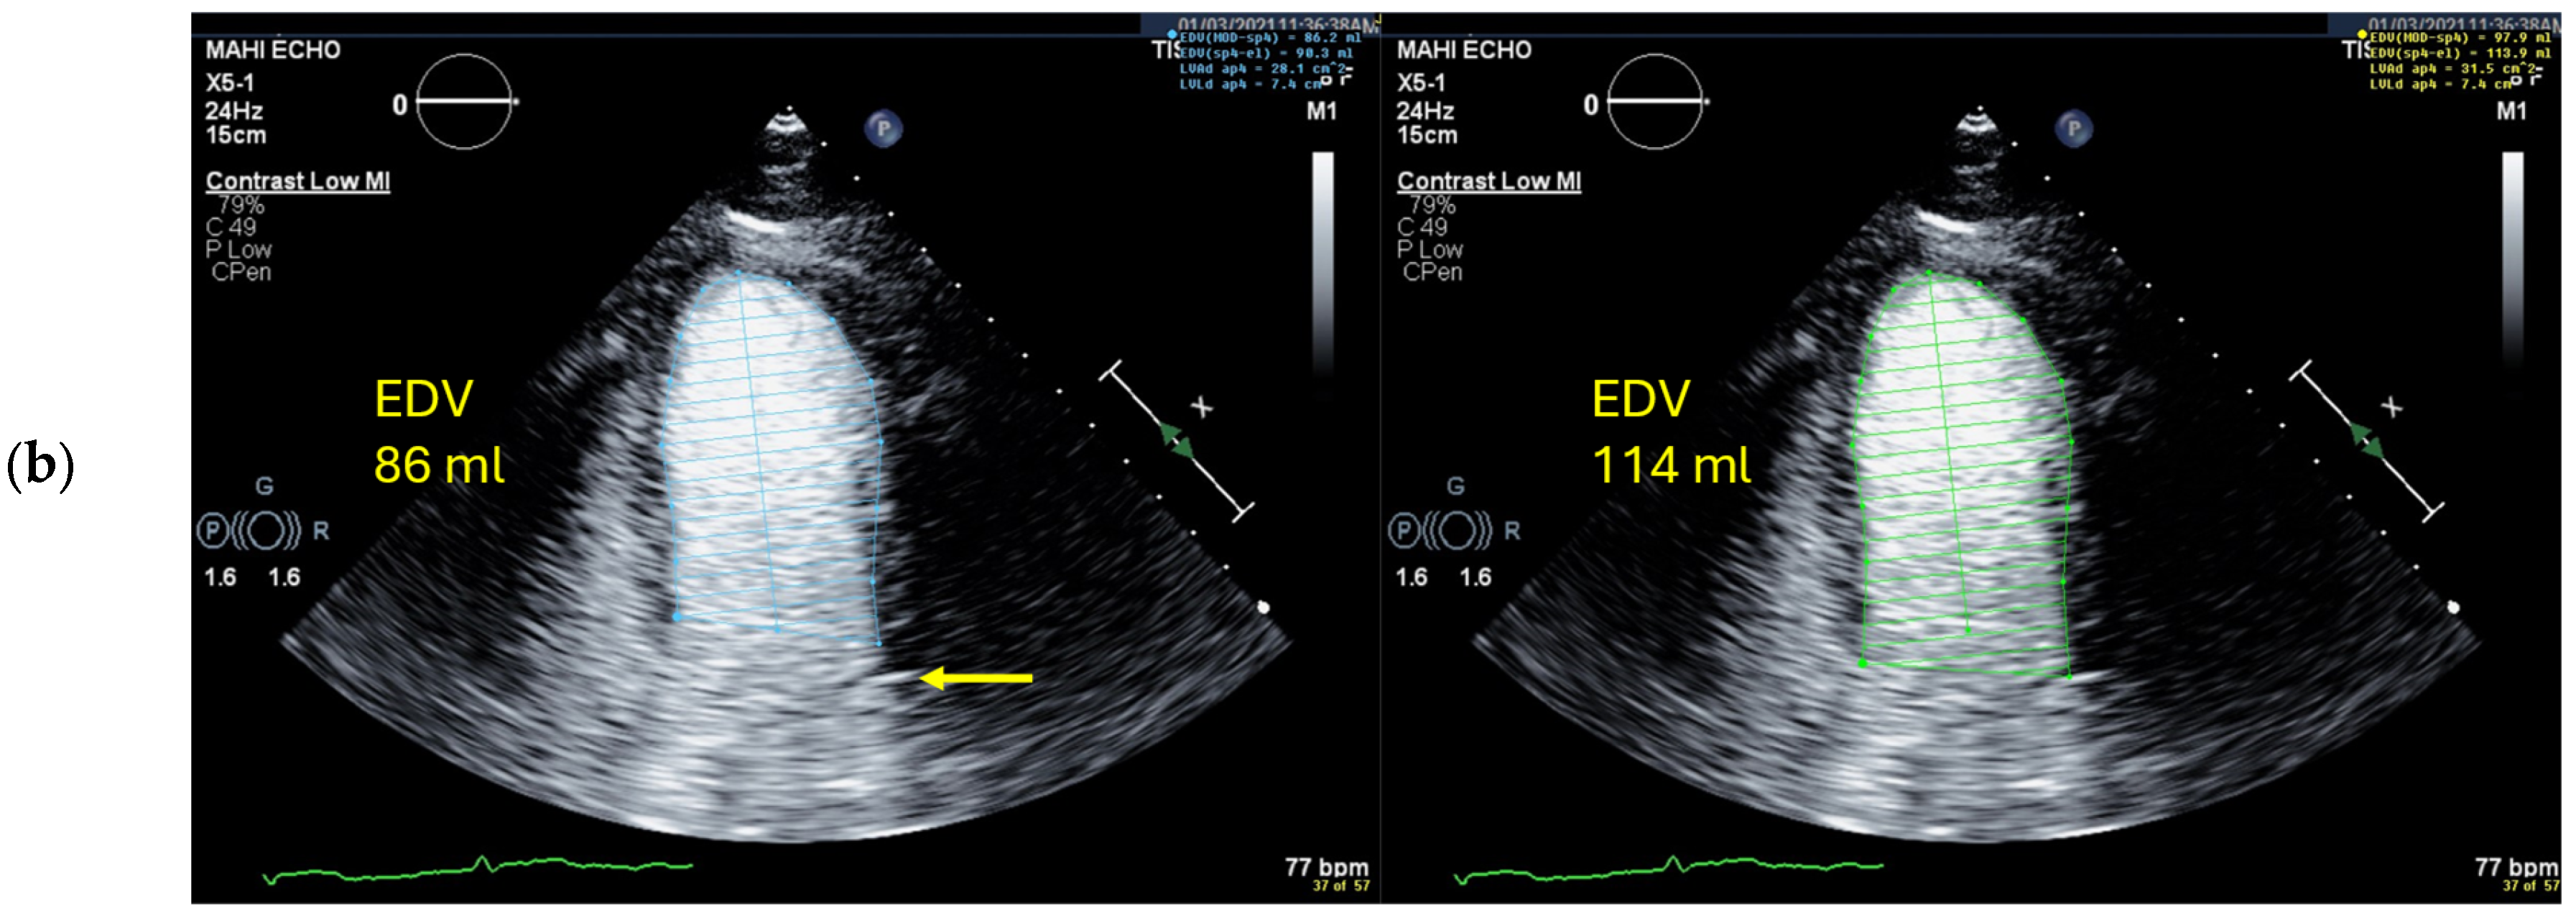

Selection of Foreshortened Loops

Selection of False End-Diastolic and End-Systolic Frames

Starting Point for the LV Contour at the Mitral Valve Ring Is Incorrect

Wrong Contour/Papillary Muscle